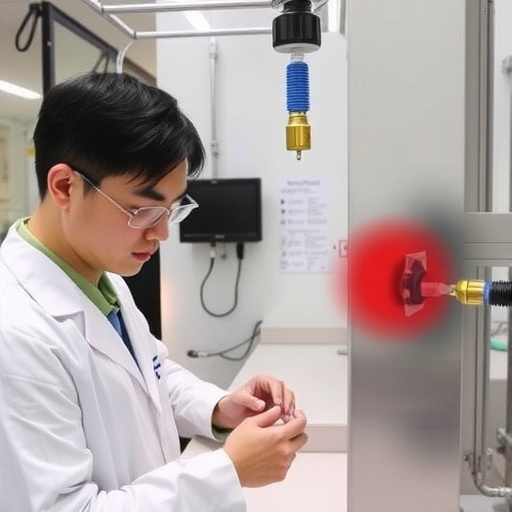

The development of this newly integrated sensor, led by Dr. Yei Hwan Jung, represents a significant shift in how healthcare providers can monitor patients who have undergone this critical procedure. Dr. Jung, an Associate Professor at Hanyang University in South Korea, emphasizes the sensor’s design, which integrates seamlessly with the standard stent graft without compromising its overall form or function. This capability is particularly noteworthy, as it allows for the transformation of a passive implant into an active monitoring device, addressing the silent threat of endoleaks without burdening patients with additional invasive procedures.

Moreover, Dr. Jung and his team have validated their approach through rigorous experimental studies, confirming that the sensor does not induce any adverse effects such as blood leakage. This stability under dynamic vascular conditions supports the hypothesis that such technology could be adapted for various other medical applications beyond vascular surgeries, expanding its impact on the healthcare landscape. For instance, similar technology could also be applied to other medical devices used in gastroenterological or urological procedures, further advancing patient safety in interventions across various specialties.

Image Credits: Yei Hwan Jung from Hanyang University.